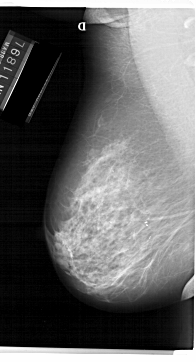

A_1230_1.RIGHT_CC

RIGHT_MLO LINES 6871 PIXELS_PER_LINE 3541 BITS_PER_PIXEL 12 RESOLUTION 43.5 NON_OVERLAY